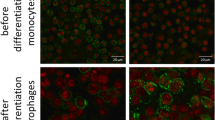

Double-labelling immunofluorescence

Acetone-fixed PBS/BSA blocked frozen sections (5 μm) from the same clinical cases were incubated with the primary rabbit antibodies against RelB or NF-IL6 combined with one or other primary mouse anti-human CD68 or RFD1 antibodies. Antibodies from two different species were used to avoid cross-reactivity. Washed sections were incubated (1 h) (rtp) with fluorescent-tagged secondary antibodies [goat anti-rabbit (1:50) (Texas red) and goat anti-mouse (1:50) (FITC)], then Vectashield mounted and viewed by fluorescence (u/v light) and laser confocal microscopy.

Double-labelling immunofluorescence

The cell types expressing NF-IL6 and RelB were identified by double-labelling immunofluorescence. Cell counting showed that a mean of 40 % of macrophages (CD68+) were activated as judged by nuclear expression of NF-IL6. 10 % of MNGC (CD68+) and no RFD1+ (antigen-presenting) cells expressed NF-IL6. By contrast, a majority of RFD1+ cells (80 %) showed RelB expression. RelB was also present in a small proportion of macrophages (10 %) and MNGC (5 %).